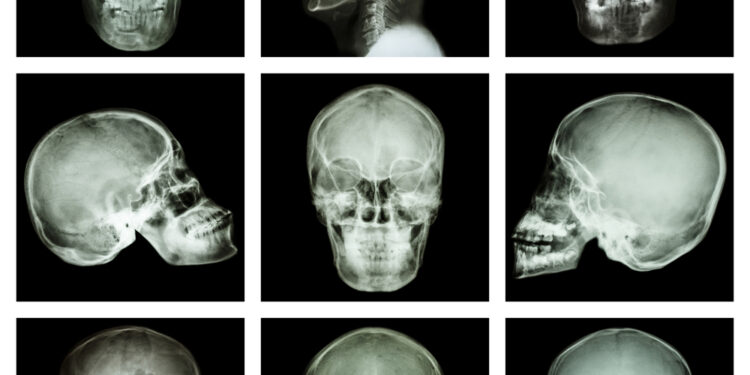

Norint tiksliau įvertinti pažeidimus, taikomi papildomi vaizdiniai tyrimai – rentgenogramos ar kompiuterinė tomografija, kurie padeda išsamiai apžvelgti pažeistas veido ir kaukolės dalis.